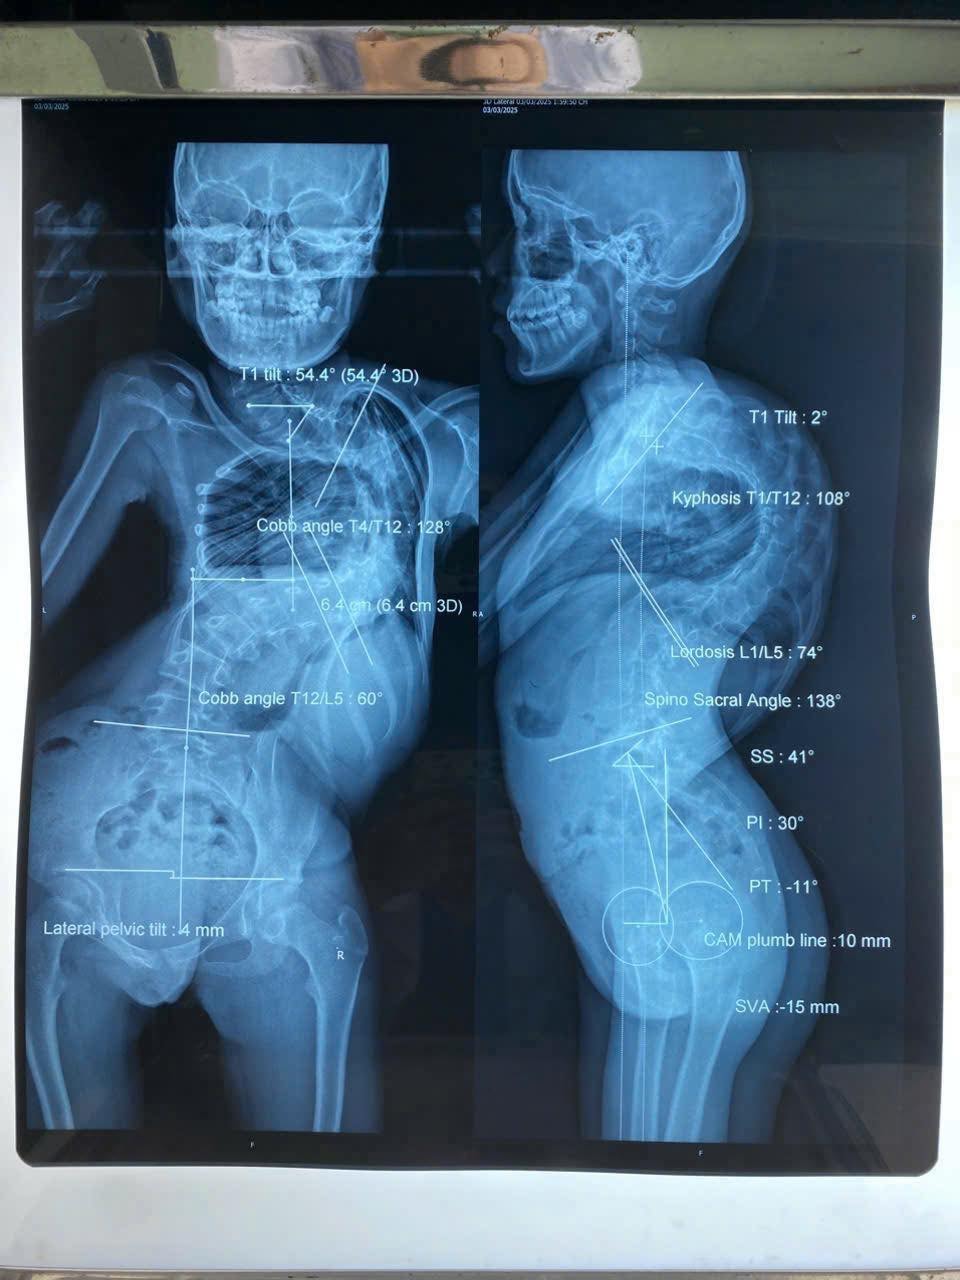

Khác với bé L , thách thức của bé Y.T (13 tuổi) đến từ thể trạng quá yếu. Bé chỉ nặng 28 kg do suy dinh dưỡng nặng, mắc hội chứng hạn chế hô hấp, cột sống cong đến 128 độ và gù 108 độ khiến lồng ngực bị chèn ép liên tục, chỉ có thể nằm sấp khi ngủ. Trước khi mổ, bác sĩ phải điều trị dinh dưỡng tích cực trong 4 tháng giúp bé tăng thêm 3 kg để đủ sức khỏe chịu đựng ca phẫu thuật.

Hình chụp cột sống bé Y.T trước phẫu thuật.Ảnh: BVCC